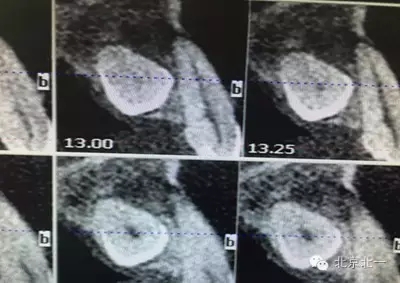

患者種植一月后種植區(qū)不適,偶有疼痛來院拍片發(fā)現(xiàn)23埋伏牙,與種植體相鄰,如圖一、二、三、四所示。

本病例建議:北一種植王明老師建議拔除埋伏牙,并同期植骨,觀察植體情況。提前告知患者失敗等風(fēng)險,簽署同意書。